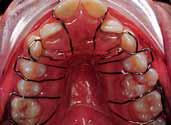

3. Anterior bite plan to reduce the overbite and bonding the lower arch (Figure 5).

The oral hygiene of the patient and the carious lesions were addressed prior to the start of the fixed appliances treatment. The patient’s compliance was good and treatment progressed without encountering major problems. The reduction of the overbite was achieved initially with the anterior bite plane then a reverse curve of Spee was placed in the lower archwire to control the overbite. A Trans-Palatal Arch (TPA) with Nance button was fitted prior to the extraction of the upper premolars in order to reinforce the anchorage (Figure 6). The treatment continued with the use of Class II traction on both sides and space closure mechanics.

The treatment of the case was planned in stages. Stage one consistedof improving the oral hygiene of the patient and management of all carious lesions and assesses the compliance and attitude of the patient towards orthodontic treatment. The next stage involved the reduction of the overbite. The patient presented with a deep overbite that was causing damage to the palatal mucosa (Figure 2). This was achieved with an anterior bite plane removable appliance and bonding of the lower arch. This appliance will free the occlusion of the buccal segment teeth and if worn consistently, will “passively” limit further eruption of the incisors but allow the lower premolars to erupt, thus reduce the increased overbite (Figure 5).

The next phase of treatment involved the fitting of the Trans-Palatal Arch (TPA) and the removal of the upper first premolars. Because of the increased overjet, this was a case of maximum anchorage and any mesial movement of the upper buccal segments was not desirable (Figure 6). It remains equivocal in the literature whether TPA appliances can provide anteroposterior anchorage. In fact, recent evidence suggested the contradictory 8 Alternatively the anchorage issue in this case could have been addressed with a Temporary Anchorage Device. The increase